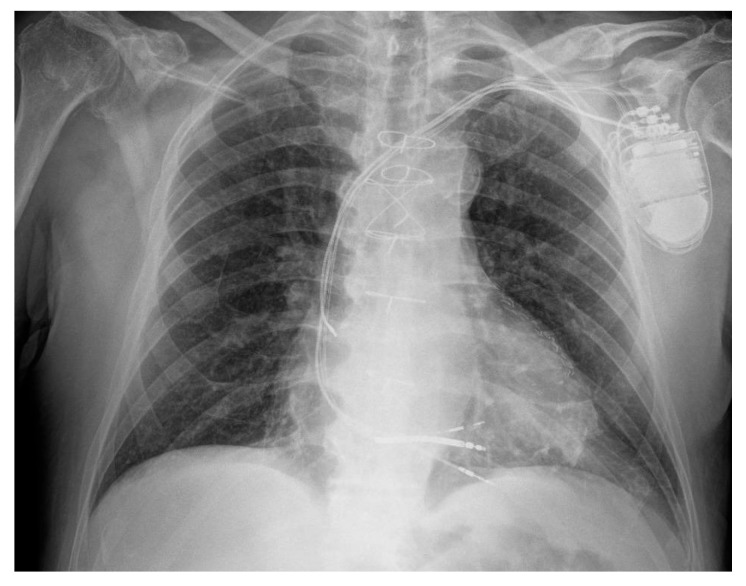

Anodal capture, characterized by a different QRS morphology compared to cathodal capture, is a well-known issue in cardiac resynchronization therapy (CRT). Left bundle branch area pacing (LBBAP), a novel physiological pacing technique, is also used as a bailout strategy following failed conventional CRT implantation. In LBBAP, QRS transition, defined by a change in paced QRS morphology, serves as a key marker of successful lead placement. This case report is the first to document both high-output anodal capture and LBBAP-induced QRS transition in a single individual receiving LBBAP with an implantable cardioverter-defibrillator (ICD) as a bailout strategy for failed cardiac resynchronization therapy with defibrillator (CRT-D) implantation. Their coexistence underscores unique device optimization challenges in this emerging approach.